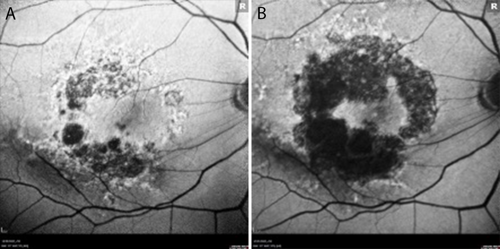

At baseline, best-corrected visual acuity (BCVA) was 20/40 in each eye. Color fundus photography (Figure 1) and fundus autofluorescence (FAF) imaging (Figure 2) revealed bilateral geographic atrophy (GA) secondary to dry age-related macular degeneration (AMD). The right eye demonstrated a moderate multifocal nonsubfoveal GA with hyperautofluorescent borders, a hallmark of active progression. The left eye showed large and numerous central drusen with pigmentary changes and only very mild atrophy. No choroidal neovascularization was present in either eye.

Throughout more than 2 years of treatment OD and 9 months OS, VA has remained stable at 20/40 bilaterally. FAF imaging at approximately 2 years demonstrates continued GA enlargement OD, though with preservation of a central foveal island (Figure 2b). OCT confirms stable foveal architecture despite peripheral atrophic progression (Figure 3). No adverse events have been observed, and the patient continues his active lifestyle.